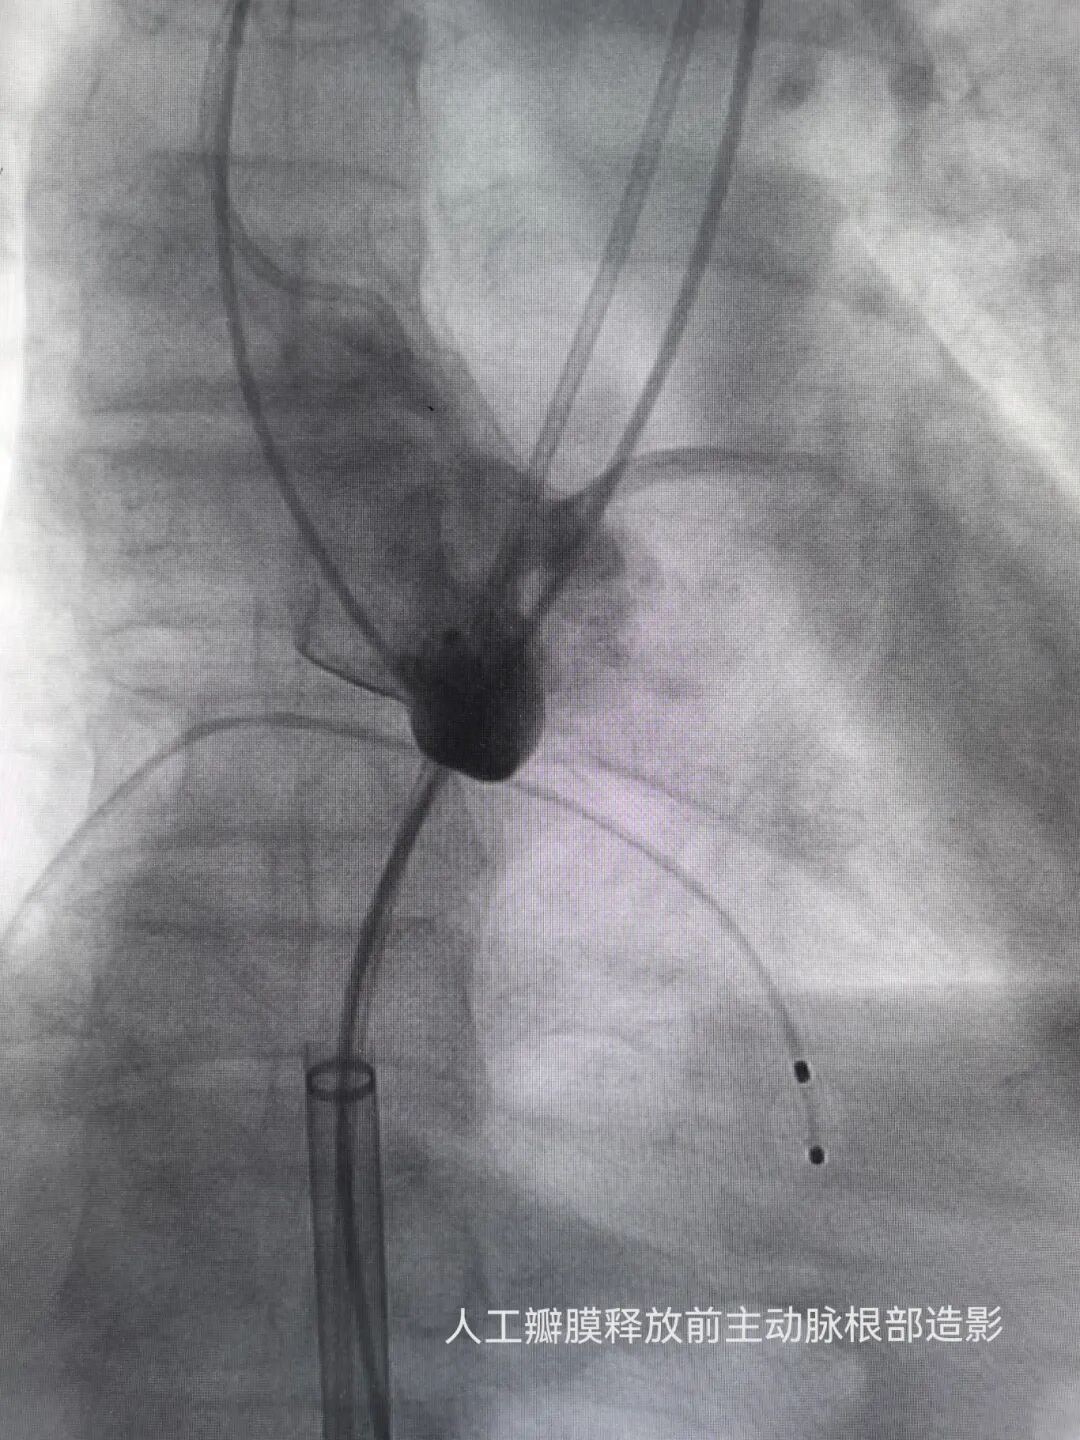

手术当日,在中山大学第一附属医院广西医院袁军教授的指导下,河池市第三人民医院心血管内科手术团队通过股动脉穿刺建立微创通路,将人工瓣膜精准送达患者病变主动脉瓣位置,在临时起搏器保护及实时造影监测下完成瓣膜释放。整个手术历时仅1小时余,术中患者生命体征平稳,几乎无明显出血。术后复查显示,人工瓣膜启闭功能良好,平均跨瓣压差降至15mmHg,术后症状明显好转。

术前术后